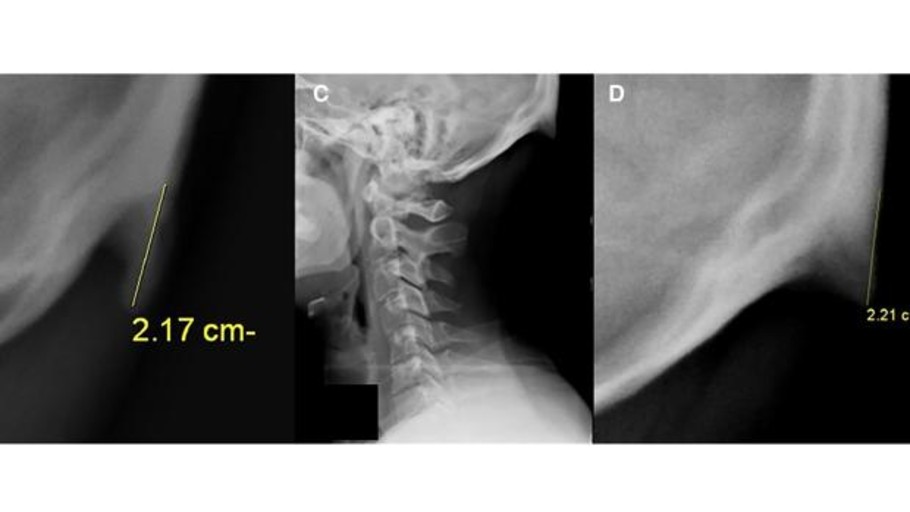

A los humanos nos está saliendo una espina en el cráneo, y los móviles tienen la culpa

Muchas personas están desarrollando un extraño «pico» de hueso justo encima del cuello quizás para sostener el peso del cráneo al bajar la vista hasta estos dispositivos